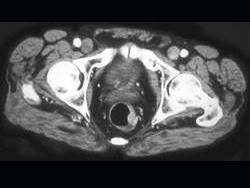

问题 男性,41岁,血便,肛诊触及左侧直肠壁一质硬小结节,结合CT所见应考虑为 ( )

选项 A、直肠转移瘤 B、直肠间质瘤 C、直肠癌 D、直肠息肉 E、直肠腺瘤

答案 C